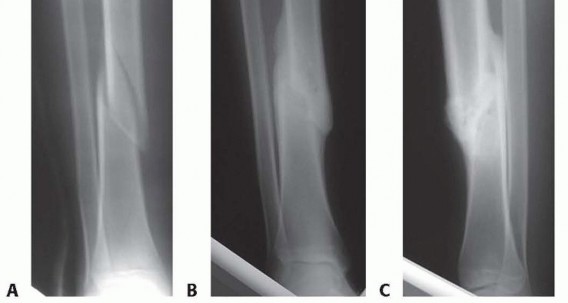

### FIG 1 • A. The metaphyseal segment extends with knee flexion secondary to the pull of the patellar tendon. B. The anterior tibial crest is palpable and represents the vertical lateral border of the tibia. Palpation of the crest can help aid in starting wire orientation. C. Anterior neurovascular structures are at risk during anterior placement of distal interlocking bolts; internal rotation may decrease the risk of arterial injury. A detailed neurovascular examination is critical to avoid the devastating complications associated with compartment syndrome, which can occur in both closed and open fractures (see Cha 53). ## IMAGING AND OTHER DIAGNOSTIC STUDIES Full-length anteroposterior (AP) and lateral plain radiographs are necessary to adequately evaluate the tibia and fibula. Complete orthogonal views of the tibia and fibula help evaluate for concurrent fractures or dislocation and any preexisting deformity or implants. Orthogonal radiographic views of the knee and ankle are required to rule out articular involvement. Axial computed tomography (CT) scan can be used for proximal and distal fractures to rule out intra-articular fracture extension. Nondisplaced fracture lines are common. Gunshot wounds may merit CT evaluation to rule out intra-articular bullet fragments and intra-articular fracture extension. Magnetic resonance imaging (MRI) is not useful for most diaphyseal or metadiaphyseal fractures. Ankle-brachial index (systolic pressure in injured leg below injury divided by systolic pressure of the brachium) after fracture reduction should be used to rule out vascular injuries in severely displaced fractures or fractures with severe soft tissue injury. Values of less than 0.9 may be indicative of vascular injury, requiring further investigation. 18 549 Compartment pressure evaluation with a commercially available handheld single-stick monitor or with a sideported catheter connected to a pressure monitor (using the arterial line setup) is indicated in patients who have severe or increasing swelling and are not able to comply with physical examination and questioning. Observe for early signs of compartment syndrome in all patients with tibial diaphyseal fractures. Open fracture does not preclude development of compartment syndrome. Measure the pressure difference between the diastolic pressure and the intracompartmental pressure—a differential value of less than 30 mm Hg is considered an indication for a four-compartment fasciotomy. 17 ## NONOPERATIVE MANAGEMENT Nonoperative management is indicated in ambulatory patients for closed and open fractures that do not require flap coverage and that do not present with excessive initial shortening or unacceptable angulation when a cast is applied ( FIG 2). An intact fibula with an axially unstable fracture pattern (ie, short oblique, butterfly fragment, or comminuted) is at risk for shortening and varus deformities and is a relative contraindication to nonoperative management. A higher rate of malunion and nonunion with nonoperative management is seen in higher energy fractures. 2, 9 Joint stiffness, especially hindfoot, is common with all forms of prolonged immobilization. 7, 22 Initial treatment includes ˜2 weeks of a long-leg splint, then a long-leg cast for 2 to 4 weeks. When the initial swelling has subsided, the patient is graduated to a patellar tendon or functional brace. Weight bearing is allowed and encouraged.

### FIG 2 • A-C. An oblique diaphyseal tibial shaft fracture treated nonoperatively to union. (Courtesy of Paul Tornetta III, MD.) Radiographs are evaluated at 1- to 2-week intervals over the first month of treatment to confirm maintenance of acceptable alignment. ## SURGICAL MANAGEMENT